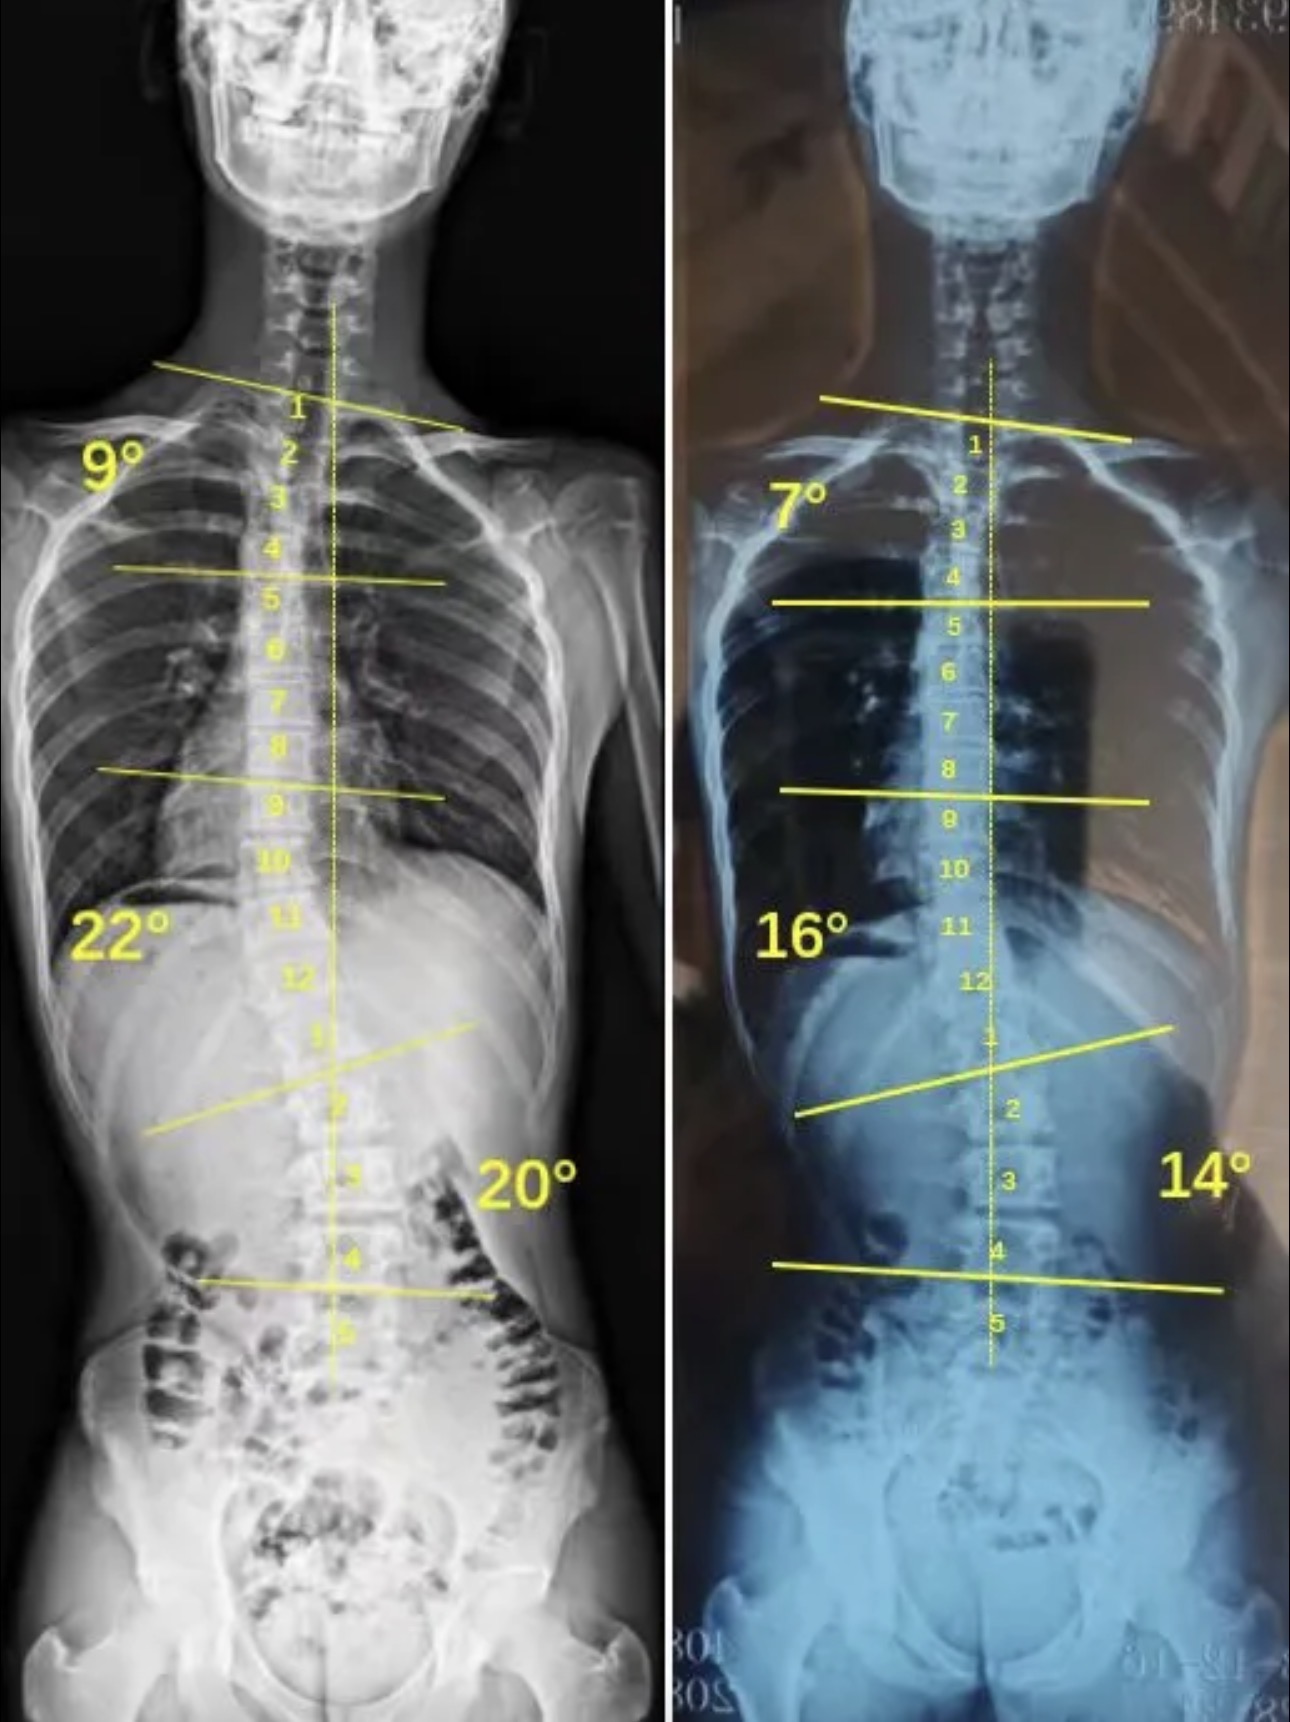

衷德脊柱,我们只关注侧弯保守治疗~

Zhongde Spine, bending no breaking ~